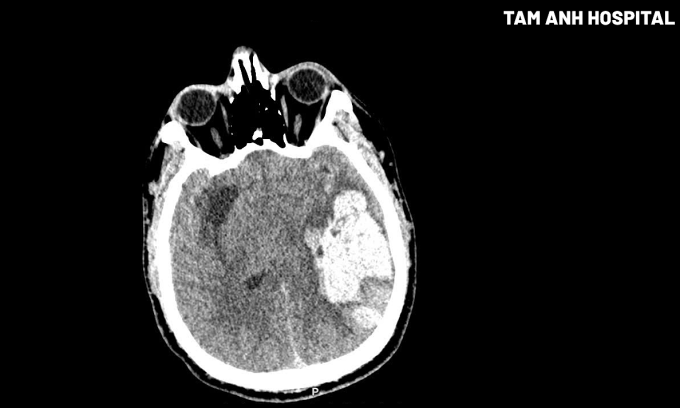

Kết quả chụp CT cho thấy bệnh nhân có ổ tụ máu nhu mô não thùy thái dương đỉnh trái kích thước 40×45×81 mm, chèn ép não thất cùng bên, lệch đường giữa 7 mm sang phải, thoát vị hồi hải mã trái (một phần hồi hải mã ở thùy thái dương trái bị đẩy lệch xuống dưới và vào trong, chui qua dưới liềm đại não). Tiến sĩ, bác sĩ Nguyễn Đức Anh, Trưởng khoa Ngoại Thần kinh Cột sống, chẩn đoán anh Đức xuất huyết não do tăng huyết áp giờ đầu, tình trạng rất nặng.

Sau 30 ngày kiểm soát huyết áp chặt chẽ, giảm phù não, kháng sinh dự phòng nhiễm trùng, sức khỏe anh Đức ổn định, vết mổ hết phù, tri giác cải thiện, chức năng vận động dần hồi phục. Kết quả chụp CT kiểm tra cho thấy khối máu tụ đã được lấy sạch, đường giữa trở lại bình thường, não thất chỉ còn ép nhẹ. Hiện, người bệnh tiếp tục điều trị phục hồi chức năng với bài tập thiết kế riêng.